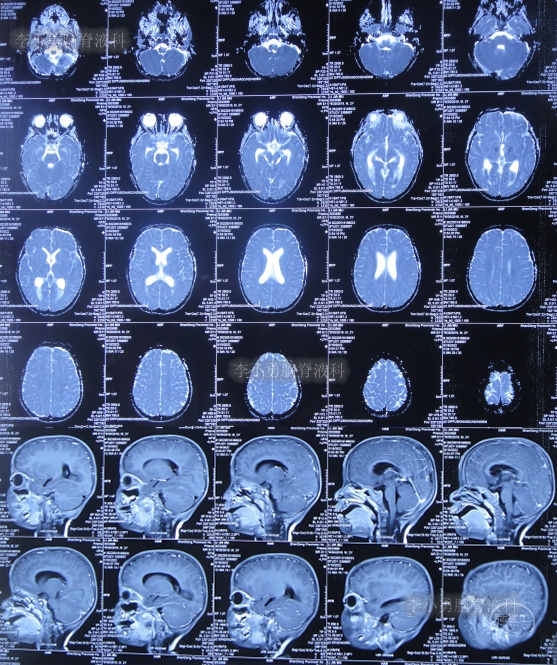

入院当天查头颅CT示脑室扩张(图-8)。

图-8:2022年7月1日入院时头颅CT

入院次日进行了脑室外引流术(图-9);引流出的脑脊液浑浊有絮状物(图-10)。

图-9:2022年7月2日头颅CT